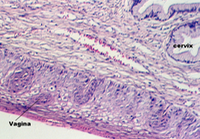

The uterus communicates with the outside world via a short canal called the cervix. The following photograph shows the uterus in the proliferative stage. The glands continue into the cervix in the left side of the photo.

Moving toward the vagina, one can see the abrupt transition between the cervical glands and the stratified squamous epithelium of the vagina. The region showing the vaginal and cervical areas juxtaposed is seen in the following photo.